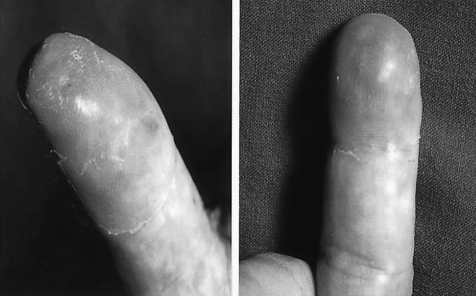

Twenty-seven months after surgery, he revisited our hospital because of painful erythematous swelling of the left thumb and the distal phalanx of the right middle finger (Figure 2). Physical examination showed that the patient had a firm, hard, painful swelling that measured 3 cm in diameter on the affected fingers. Skin biopsy from the right middle finger revealed a well-differentiated adenocarcinoma (Figure 3B). In order to confirm that this lesion originated from the primary ampullary carcinoma. and to exclude that this lesion was from other primary sites, immunohistochemical staining was performed with cytokeratin 7 (CK 7), cytokeratin 20 (CK 20), mucin 1 (MUC 1), mucin 2 (MUC 2), thyroid transcription factor-1 (TTF-1), prostate specific antigen (PSA) against the ampullary tumor and skin biopsy specimen. Both tissues were not stained with the TTF-1, PSA, MUC 2, CK 20; however, they stained positive with MUC 1 and CK 7 (Figure 3C-F). The negative result for TTF-1 and PSA supported exclusion of other primary sites (eg lung, prostate). Therefore, our findings confirmed acral metastases from the ampullary carcinoma primary.

Figure 2

Painful erythematous swelling on the left thumb and distal phalanx of the right middle finger.

Skin metastasis tends to occur in close proximity to the primary tumor4). Therefore, common sites of skin metastasis are the head, chest6), and abdomen, but metastasis to the fingers is rare7). Generally, cutaneous metastases are classified into three groups according to their appearance: nodular, inflammatory and sclerodermoid metastatic lesions4). They may appear as one or as a combination of the morphologic forms mentioned. Our case presented as an inflammatory type skin metastasis. Painful cutaneous metastasis like our case are rare7). They must be distinguished from acute suppurative inflammation, osteomyelitis, acute paronychia, foreign body granuloma, infectious hematoma, as well as tuberculosis. Based on the fact that this patient had problems with his fingers as a result of gardening work, initially his finger lesion was misdiagnosed as a foreign body granuloma caused by thorns. However, the biopsy of the inflammatory lesion revealed adenocarcinoma.